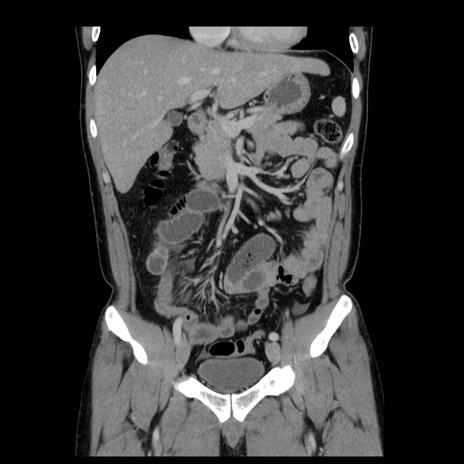

症例4(冠状断像)

【症例】30歳代男性

【主訴】腹痛、嘔吐

【現病歴】昨晩から突然の腹痛あり、その後嘔吐、軟便も出現。腹痛が改善しないため救急搬送となる。2日前にしめ鯖の食事歴あり。

【身体所見】意識清明、苦悶様、BP 135/90mmHg、BT 35.7℃、腹部:平坦、やや硬、心窩部〜臍部に自発痛、圧痛あり、筋性防御+、反跳痛-

【データ】WBC 8100、CRP 0.57